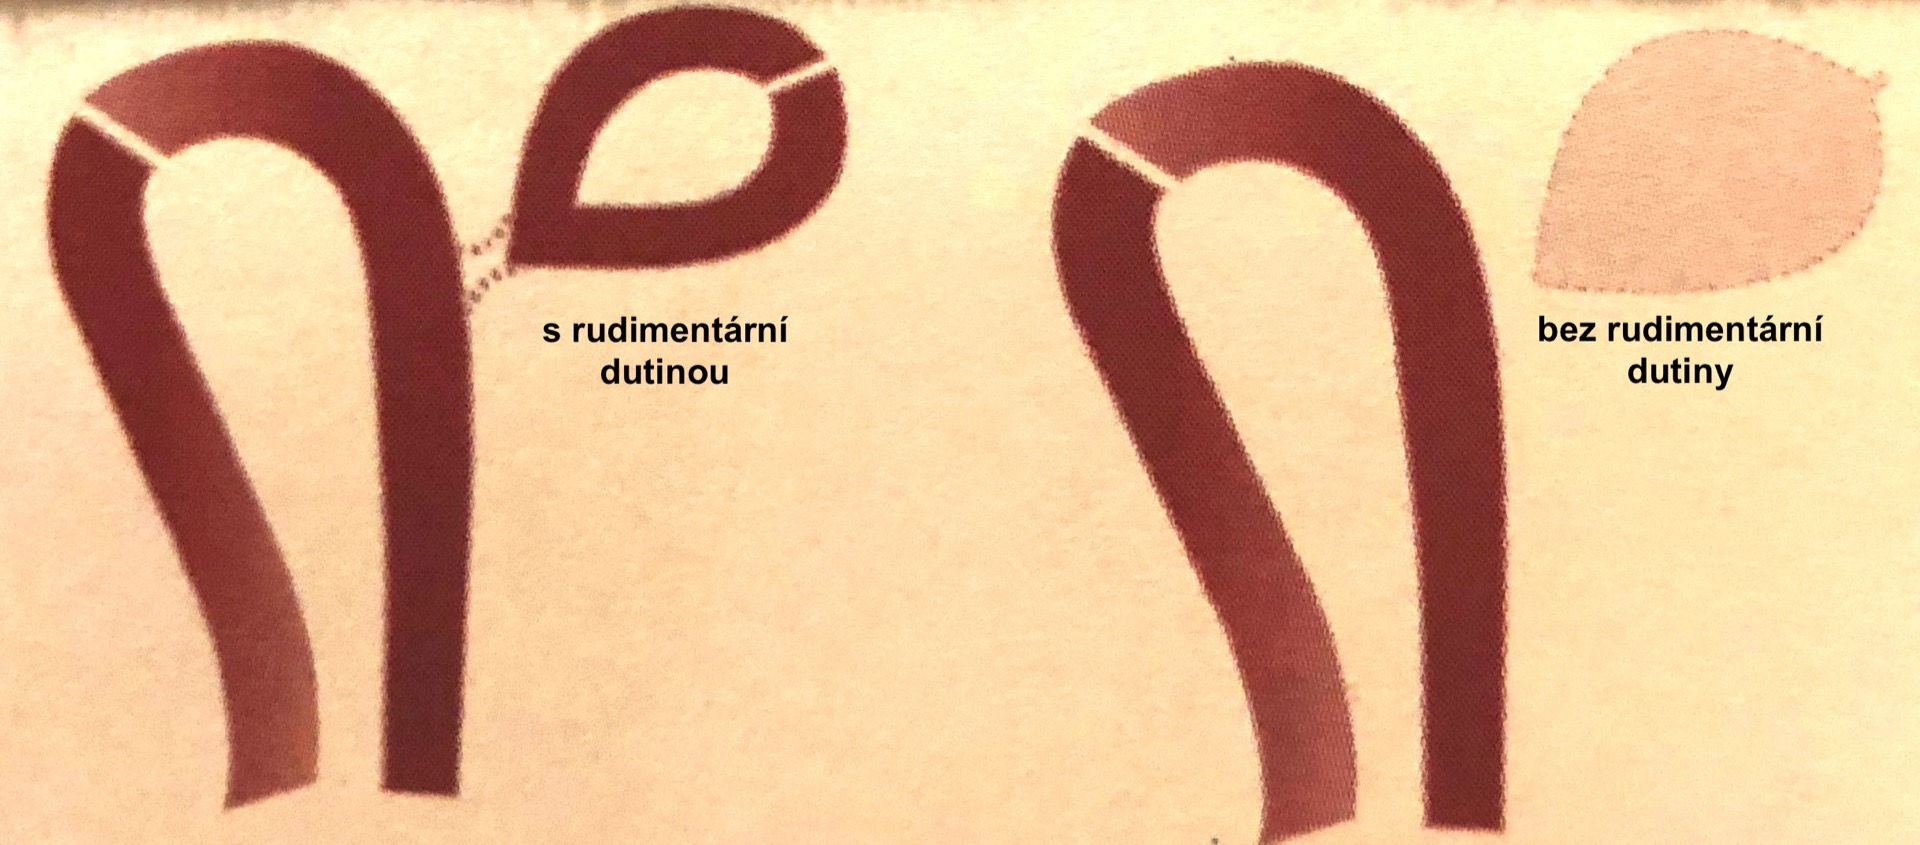

- Děloha vytvořená pouze z jednoho Müllerova vývodu. Část tvořená druhým Müllerovým vývodem je neúplně vyvinutá (rudimentární) nebo chybí-hemi uterus (dřívejší název uterus cum cornu rudimentario nebo uterus unicornis). Pro zapamatování tohoto druhu vývojové vady si můžete tvar dělohy srovnat s nějakým druhem ovoce. Pokud jste zvolily banán, je to správně.

Dozvěděla jste se od lékaře, že máte jednorohou dělohu? Neznamená to, že nemůžete otěhotnět nebo donosit těhotenství do termínu. Tato vývojová vada ale může na sebe upozornit podstatně dříve. Již při nástupu prvních menstruačních cyklů se projeví narůstajícími bolestmi v podbřišku, pokud je v rudimentárním děložním rohu i děložní dutina a chybí kanalizovaná spojka do funkční hemi dělohy (na obrázku je znázorněna přerušovanou čárou). V rudimentárním rohu se při menses hromadí krev, která nemůže odtékat a je nutné jeho laparoskopické odstranění. Odstranění je nezbytné i v případě komunikujícího děložního rohu z důvodu prevence uhnízdění oplozeného vajíčka. Takové těhotenství se chová stejně jako mimoděložní se všemi vážnými důsledky.

Aplastická děloha

Jedná se o defekt formování dělohy, při kterém děloha zcela chybí nebo v místě nedostatečně vytvořených Müllerových vývodů nalezneme pouze rudimentární děložní rohy bez nebo s děložní dutinou. Pacientky s aplastickou dělohou mohou mít i další vady, například u nich může chybět pochva nebo mají místo pochvy pouze malý důlek (syndrom Mayer-Rokitansky-Küster-Hauser).

- Aplastickou dělohu s rudimentární-funkční dutinou vidíte na prvním obrázku. Funkční děložní roh může být přítomen na jedné nebo na obou stranách. Protože chybí komunikace rudimentární dutiny do pochvy hromadí se v ní menstruační krev a žena si stěžuje na cyklické bolesti v podbřišku. Vada se řeší laparoskopickým odstraněním funkčního rudimentárního rohu.

- Při aplastické děloze bez rudimentární funkční dutiny jsou přítomny pouze zbytky dělohy nebo děloha zcela chybí. Vada se projeví nepřítomností menstruace.